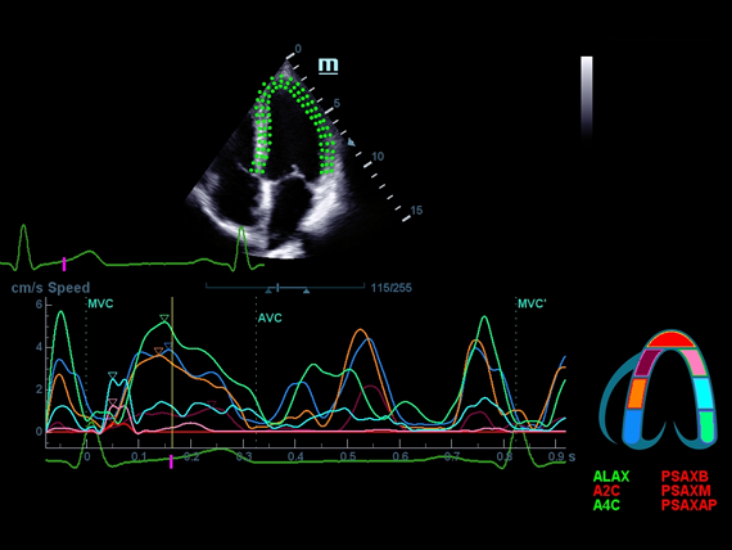

Специализированный уход благодаря ECHO

Многофункциональная система DC-60 Exp с X-Insight представляет собой комплексное решение, которое помогает управлять повседневной клинической практикой с легкостью и уверенностью.

Основываясь на глубоком понимании потребностей клиентов, компания Mindray разработала систему DC-60 Exp с X-Insight, чтобы обеспечить высокую производительность и точность визуализации вкупе с наглядностью, исключительной интеллектуальностью и огромным опытом.

Опыт работы и высокая производительность